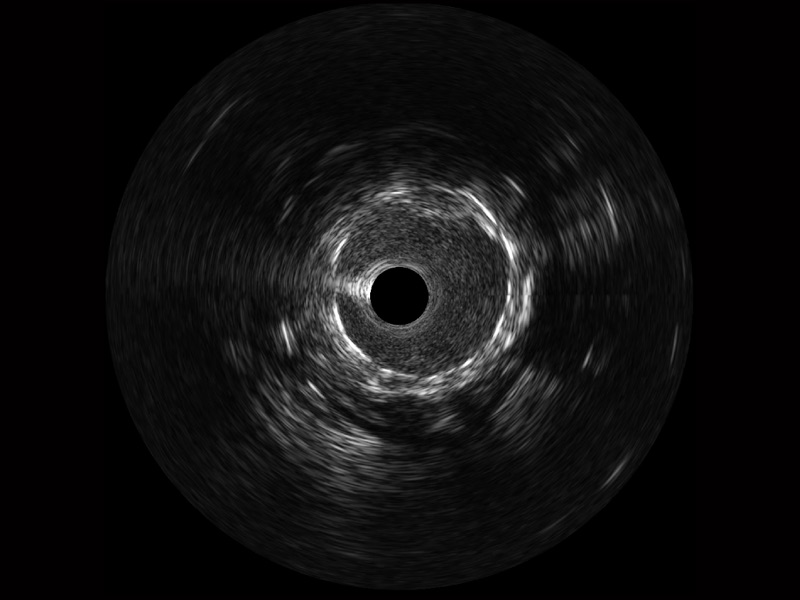

传统IVUS图像

对比传统IVUS导管成像,MILE米乐集团官网宽频IVUS图像的近场支架梁显影更细腻,远场中膜外血管仍清晰可辨,兼顾远中近,兼顾分辨力与穿透深度